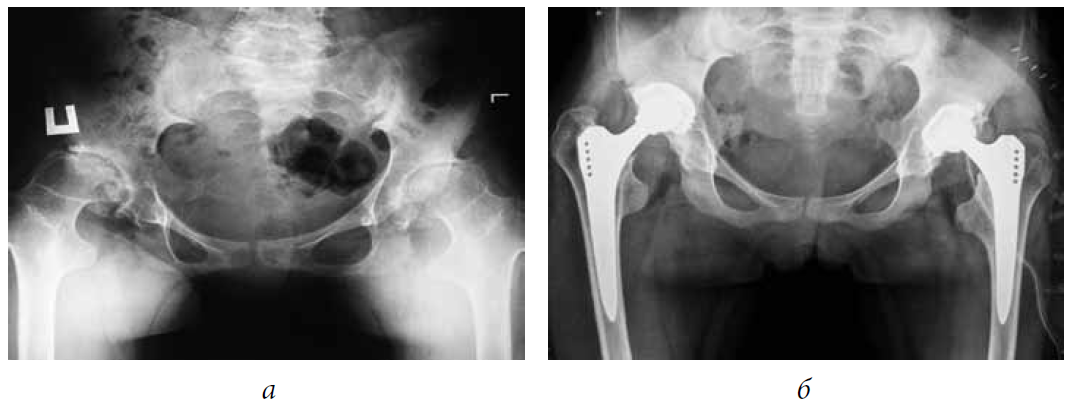

Stabilometric and plantographic studies were conducted in 12 pediatric patients with bilateral coxarthrosis, stage III, which developed as a result of HP dysplasia in 6 patients and spondyloepiphyseal dysplasia in 6 patients. The age of the patients ranged from 13 to 17 years (average age was 15.1 ± 0.47 years). The examinations were performed before (Fig. 1, a) and after (Fig. 1, b) the bilateral THR within 1–3 years. The time interval between surgeries on the contralateral joints ranged from 6 to 12 months.

Fig. 1. Radiograph of the hip joint (HP) of patient A, 16 years old. Spondyloepiphyseal dysplasia. Bilateral coxarthrosis, stage III: a — before hip replacement; b — after bilateral THR